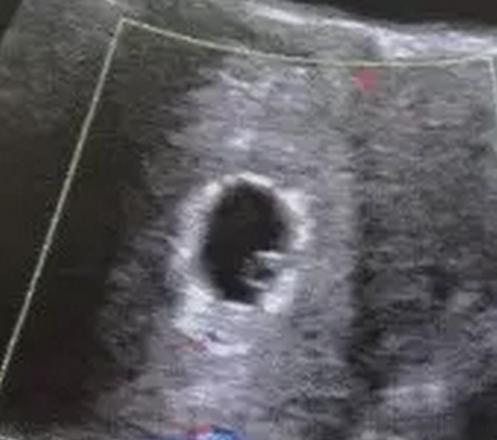

孕囊大小

30天左右的孕囊,彩超看上去就只有3~5mm一个小暗区,很难区分它到底是不是孕囊。

在胚胎着床是,由于着床侵蚀子宫内膜血管出血,在孕囊周围形成环形暗区,叫做“双环征”,这是诊断妊娠比较有特异性的依据。这个时候大概5周,孕囊大小大约1~1.5cm。

到孕7+周,孕囊 2cm,8周长到3cm。